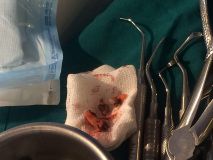

دوره آموزشي سينوس ليفت همراه با جراحي زنده

تاريخ: ٨-٩ بهمن ١٣٩٤

اساتيد:

دكتر كريمي

دكتر مشير آبادي

دكتر خليلي

دكتر عميد